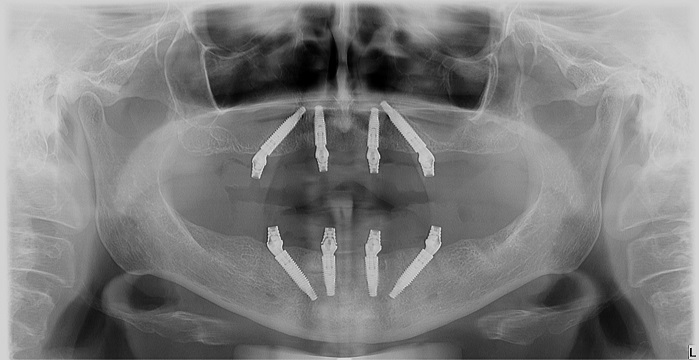

Nakon preoperativnih priprema, ako je potrebno, izvade se preostali malobrojni zubi (ako ih ima i loši su), i postavljaju se na tačno utvrdjena mesta posebni implanti, vodeći računa o okolnim anatomskim strukturama. Dva implanta se postavljaju u frontalnu regiju gde je volumen kosti veći, i gde se očekuje najmanja atrofija kosti, a druga dva implanta se postavljaju u bočnoj regiji pod uglom od 45 stepeni, kako bi budući zubi bili stabilniji, vodeći računa o bitnim anatomskim parametrima, tj maksilarnom sinusu u gornjoj i mandibularnom kanalu u donjoj vilici.